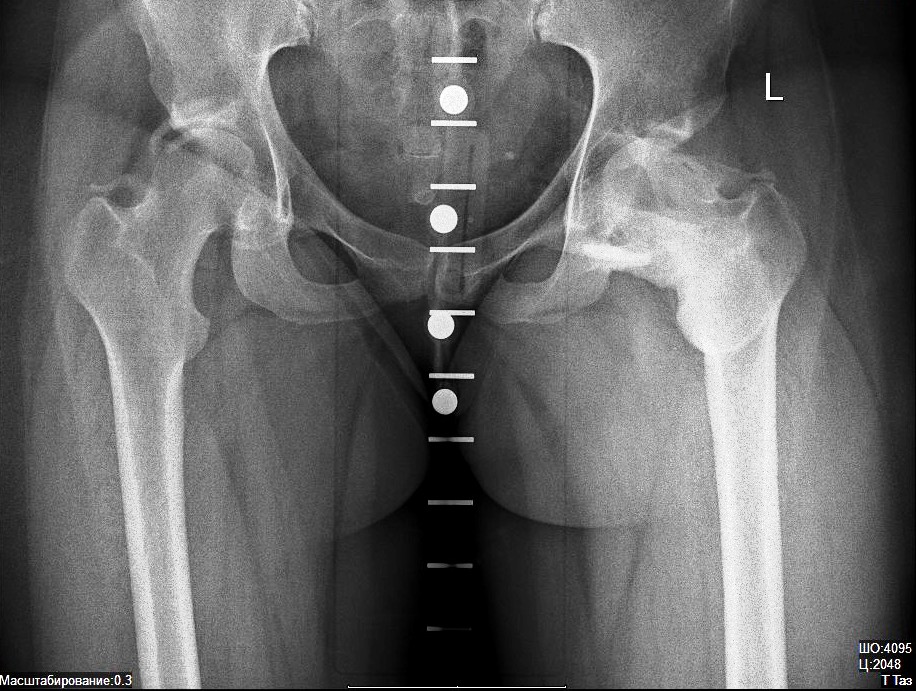

Оссификация тазобедренных суставов: что это и как проявляется?

Раздел: Сокровищница опыта